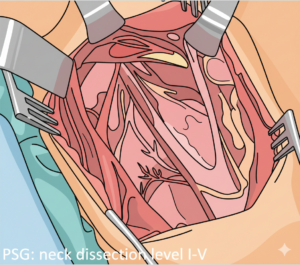

Σχηματική απεικόνιση ανατομίας τραχήλου και λεμφαδενικού καθαρισμού με χειρουργικά εργαλεία.

Καλλιτεχνική απεικόνιση της ακρίβειας που απαιτείται στον λεμφαδενικό καθαρισμό για την προστασία των νεύρων και των αγγείων.